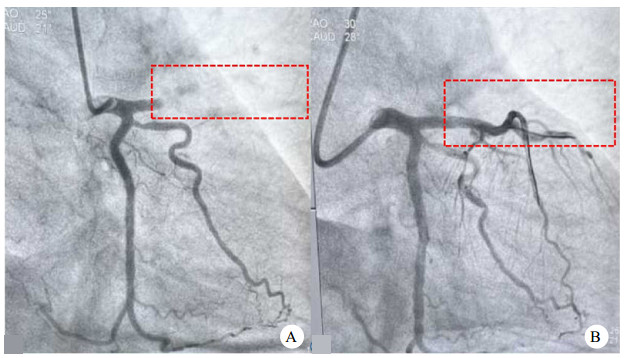

1 资料与方法患者男性,58岁,既往体健。主因“突发意识丧失20 min”由120送入本院急诊,入院时意识丧失,呼吸浅弱,小便失禁,查体双侧瞳孔4.4 mm,对光反射迟钝,周身皮肤厥冷,大动脉搏动未扪及,血压、外周血氧饱和度未测出。心电图提示室颤心律(图 1A),立即予电除颤并行气管插管机械通气辅助呼吸,多次电除颤后患者心电图可有短暂复律(图 1B), 复律心电图提示I、aVL、V1-V4导联ST段弓背向上抬高,床旁心脏超声提示左室壁节段性运动障碍,急诊POCT提示CK-MB 21.2 ng/mL,Myo 303 ng/mL,TnI 0.54 ng/mL,诊断为STEMI、顽固性室颤、心源性休克。考虑患者CCPR复苏时间长、血流动力学不稳定、出现ROSC但不能维持自主心律且病因可逆,征得家属同意后启动急诊ECPR治疗。患者接受VA-ECMO支持(附图 1A:心肺转流系统滚压式血泵WEL-H5,天津汇康医用设备有限公司,注册证编号:国械注准20203100339)、MAQUET体外循环套包(BE-PLS 2050),予负荷量普通肝素100 U/kg后监测ACT及APTT(目标ACT 180~220 s,APTT 60~80 s),经右股静脉、左股动脉分别置入21 Fr静脉导管(MAQUET,BE-PVL 2155)和15 Fr动脉导管(MAQUET,BE-PAL 1523),并持续给予普通肝素静脉泵入,根据ACT及APTT动态监测结果滴定肝素剂量。ECMO(血流量2.5 L/min,吸入氧浓度50%,气流量1.5 L/min)连接变温水箱(预设温度36℃)成功运转后患者生命体征趋于平稳(附图 1B),于稳定后转运至导管室行经皮冠状动脉介入(PCI)治疗(附图 1C)。急诊ECPR启动至ECMO运转时间为30 min,ECMO运行期间采用保护性肺通气策略。冠状动脉造影(CAG)提示左前降支近段100%闭塞(图 2A),术中开通前降支,植入Promus Premier 2.75×28.00 mm支架1枚,复查CAG提示左前降支完全再通(图 2B)。经右股动脉植入IABP。术后患者生命体征平稳,逐渐降低ECMO参数,于ECMO流量降至0.5 L/min生命体征平稳后停止ECMO运行,观察20 min无异常后撤除ECMO。ECMO运行总时长为4 h。术后转入急诊EICU,心电图提示前壁导联ST段明显回落(图 1C), 予机械通气、IABP、抗凝、抗血小板聚集、抗感染、营养支持及镇痛镇静等治疗。术后第1天心脏彩超提示左室射血分数(left ventricular ejection fraction, LVEF)33%,第2天患者意识恢复正常,第3天撤除机械通气,第5天复查心脏彩超提示LVEF 48%,撤除IABP,第8天患者出院,心电图提示ST-T改变明显好转(图 1D),未遗留任何中枢神经系统并发症。本例国产ECMO使用属于上市后应用,应用前取得了患方的知情同意,并经过天津医科大学总医院医学伦理委员会审批(审批号:IRB2021-YX-240-01)。

| A:冠脉支架植入前冠脉造影显示左前降支近段100%闭塞; B: 冠脉支架植入后冠脉造影显示左前降支完全再通(虚线框内为冠脉造影左前降支闭塞及再通情况) 图 2 急诊冠状动脉造影及经皮冠状动脉介入治疗前后 |